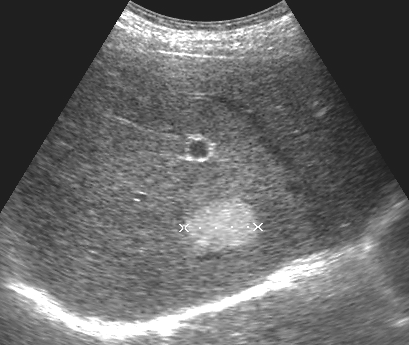

Как выглядит доля Риделя на УЗИ печени